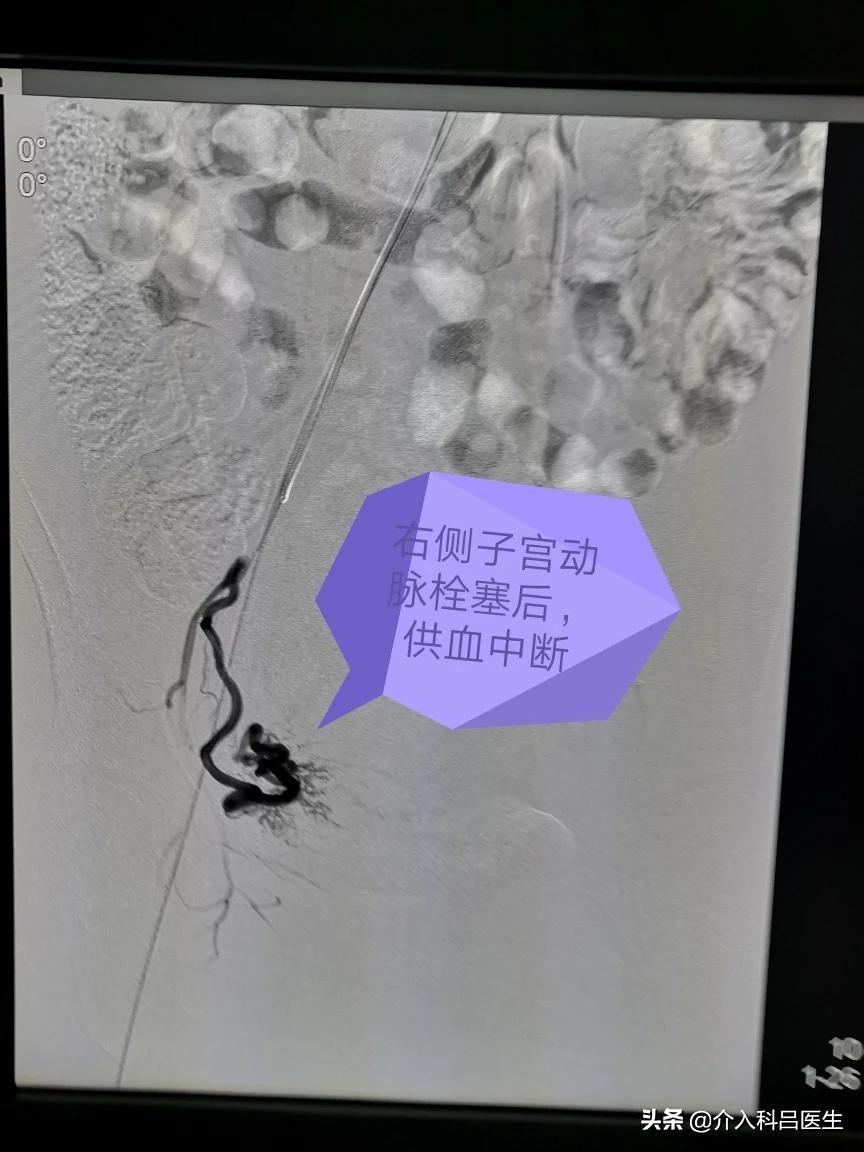

打眼一看就是典型的南方人面孔,可是脸色苍白,典型的贫血貌,心率明显快,血压有点低,都是肌瘤贫血引起的,双侧子宫动脉供血很丰富,栓塞很彻底,只留下子宫动脉主干,肌瘤缺血坏死萎缩吸收,子宫由于还有其他血管供血,不至于坏死,大概半年后子宫就能够恢复正常了。

术后